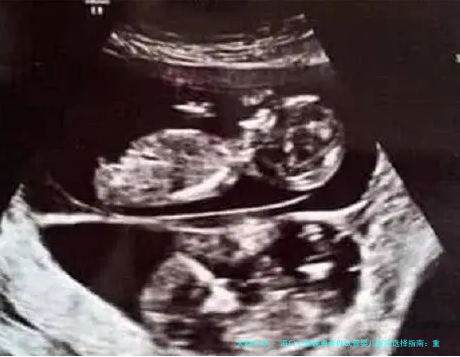

选医院时,心脏病患者应首先思量那些设有强大心思精力管内科或心脏中心,且生殖医学科能够发展第三代试管婴儿技术的机构。这能保证在孕前、孕中、孕后都能得到心脏功能的严密监护,并通过胚胎植入前基因学检测降低遗传性心脏病传给下一辈的风险。